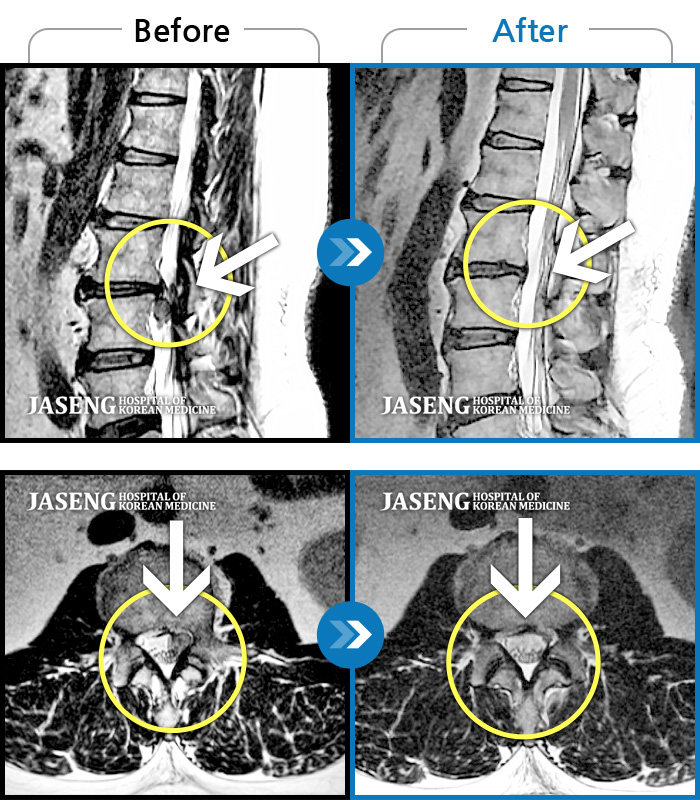

MRI 치료사례

허리 숙일 때, 앉을 때, 보행시 허리 통증 증가, 좌측 발목~무릎부위 통증